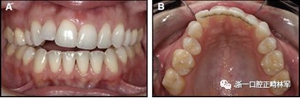

圖13.粘合到尖牙和切牙上的柔性螺旋弓絲保持器,伴有牙齦退縮和附著喪失,中切牙之間嚴重的扭矩差異以及兩顆尖牙的橫向移動和扭矩。牙周問題和牙齒移動的嚴重程度均為牙周正畸聯(lián)合治療的指征:A,正面視圖; B,咬合面視圖。

圖14.三維立體圖像:A,面部和B,切牙根部的舌側,剛取出固定舌側保持器后。